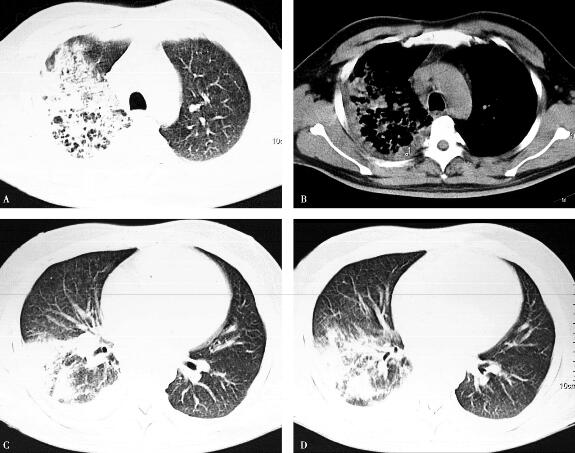

治疗10天后,咳嗽、咳痰症状逐渐消失,肺部听诊未闻及湿啰音,体温正常,消化系统、神经系统症状消失,胸部CT较前略有吸收(图3)。治疗两个月后,随访:无不适症状,胸部CT病变明显吸收(图4)。

图4